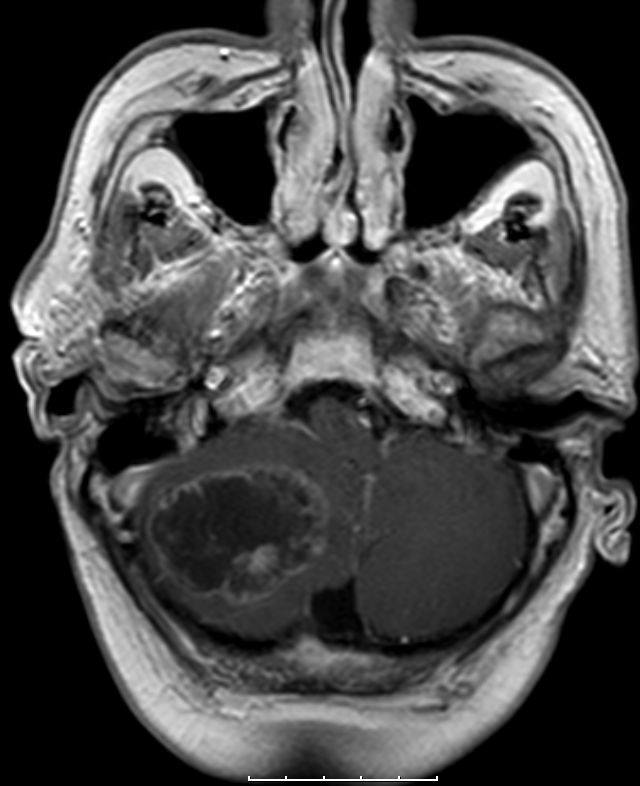

Hirnmetastasen 72-jähriger Mann, der 1 Jahr nach einem Caecumkarzinom cT3 cNo G3, eine Kleinhirnmetastase entwickelte. Abdomen und Leber frei.

CT nach KM-Gabe und MRT:

MRT: